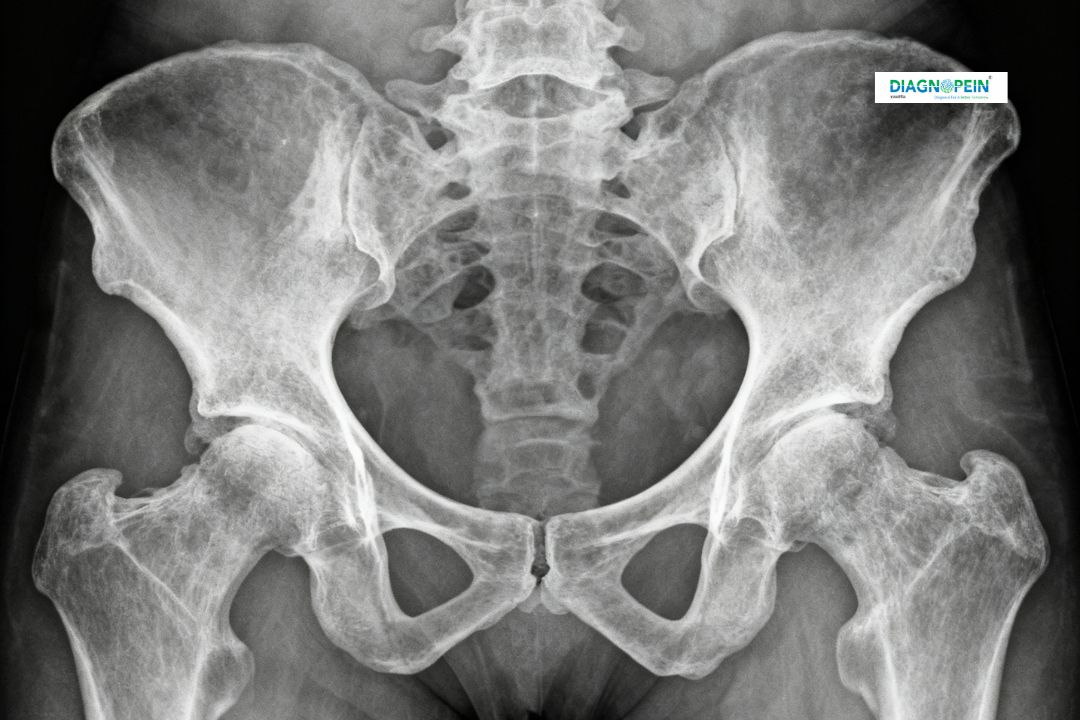

X-Ray Pelvis AP (Anteroposterior View) is one of the most common and essential radiographic tests used to examine the bones and joints of the pelvic region. At Diagnopein Diagnostic Center in Karad, this advanced imaging technique helps doctors analyze the structure, alignment, and any possible injury or abnormal condition in the pelvis region. The process uses low-dose radiation to create a clear image of the pelvic bones, including the hip joints, sacrum, and coccyx, ensuring early detection and accurate treatment planning.

The X-Ray Pelvis AP is a critical diagnostic tool for evaluating injuries, joint degeneration, or bone disorders within the pelvic area. It helps detect fractures, dislocations, bone deformities, arthritis, or infections. For patients with lower back or hip pain, this scan helps physicians determine the root cause effectively.

The procedure for an X-Ray Pelvis AP is simple and comfortable. The patient is asked to lie flat on the X-ray table with legs slightly rotated inward to get a proper front (anteroposterior) view of the pelvis. A lead apron is used to shield other parts of the body from unnecessary radiation exposure. Once positioned, the X-ray beam passes through the pelvis area while images are captured digitally. The entire process usually takes less than 10 minutes.